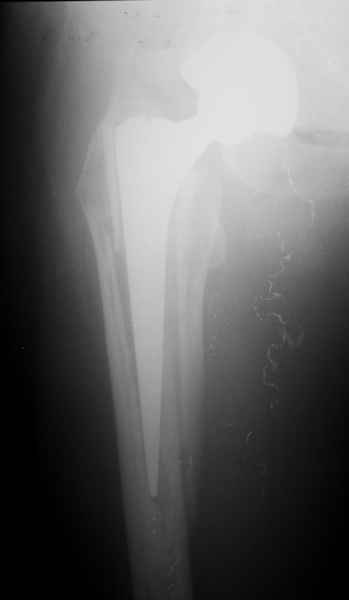

Хочется показать два подобных случая, П-ка Зубарева 72 лет и п-т Гладковский 80 лет. Сразу принимаю замечание, что это были ножки цементной фиксации, просто под руками не было бесцементника.